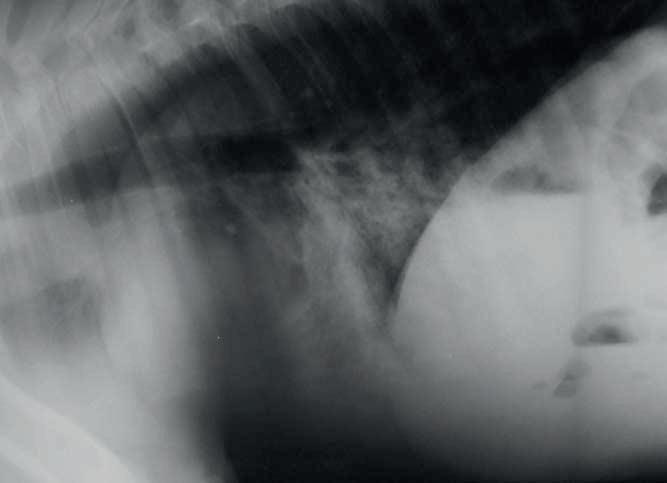

El estudio radiográfico muestra campo pulmonar con prominentes broncogramas. Este patrón se observa también en SADR previo a complicación séptica y deficiencia de surfactante en potros prematuros, cuando hay aspiración el campo pulmonar muestra un patrón alveolar que ocupa y obscurece la silueta cardiaca caudal (Wilkins, 2003).

Radiografía Torácica de potro neonato con neumonía viral. Patrón alveolar distribuido en todo el campo pulmonar con prominentes broncogramas. Este patrón se observa también en SADR previo a complicación séptica y deficiencia de surfactante en potros prematuros (Wilkins,2003).